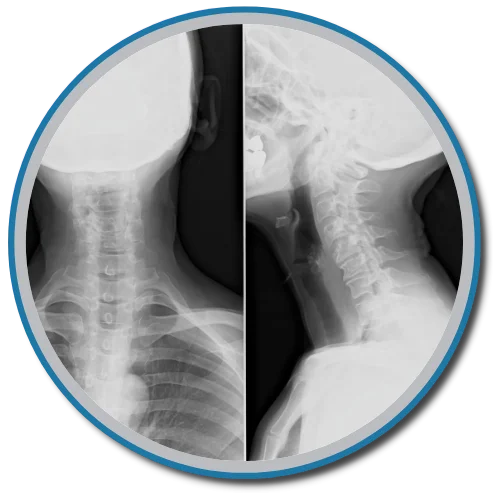

Chiropractors take x-rays to see the internal condition of the spine. X-rays also reveal if there are any underlying spinal disorders, such as arthritis of the spine, abnormal development, disc disorders, bone spurs, and spinal deterioration.

Having an x-ray taken before any adjustment helps chiropractors make a correct diagnosis. Combining x-rays with other exams will benefit the patient ultimately.